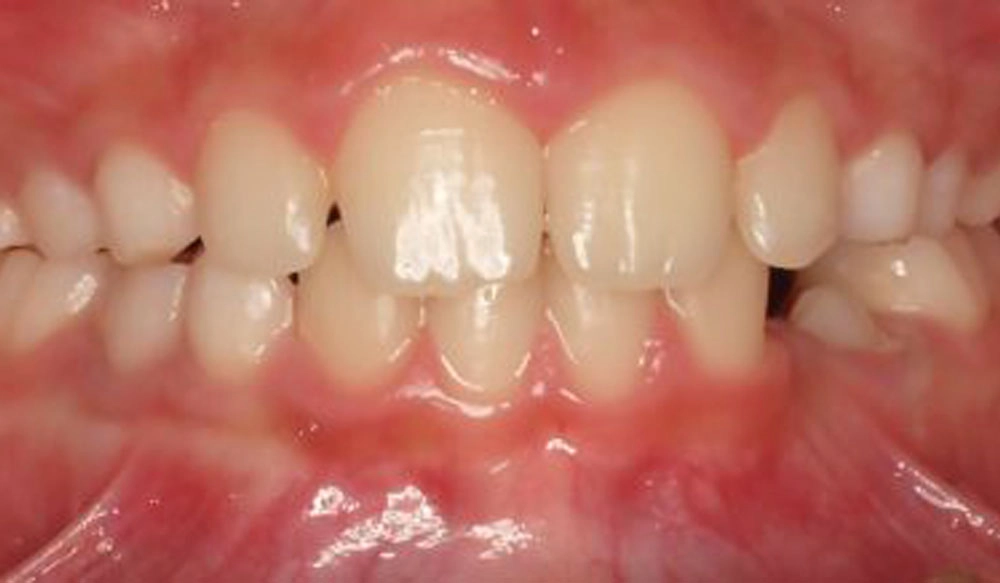

Crowding

Crowding is the condition in which there is a discrepancy between tooth size and space available for the teeth to be aligned in the dental arch

Patient Information:

Age: 17

Gender: female

Invisalign Treatment Option: Invisalign Comprehensive

Total Treatment Time:

29 months